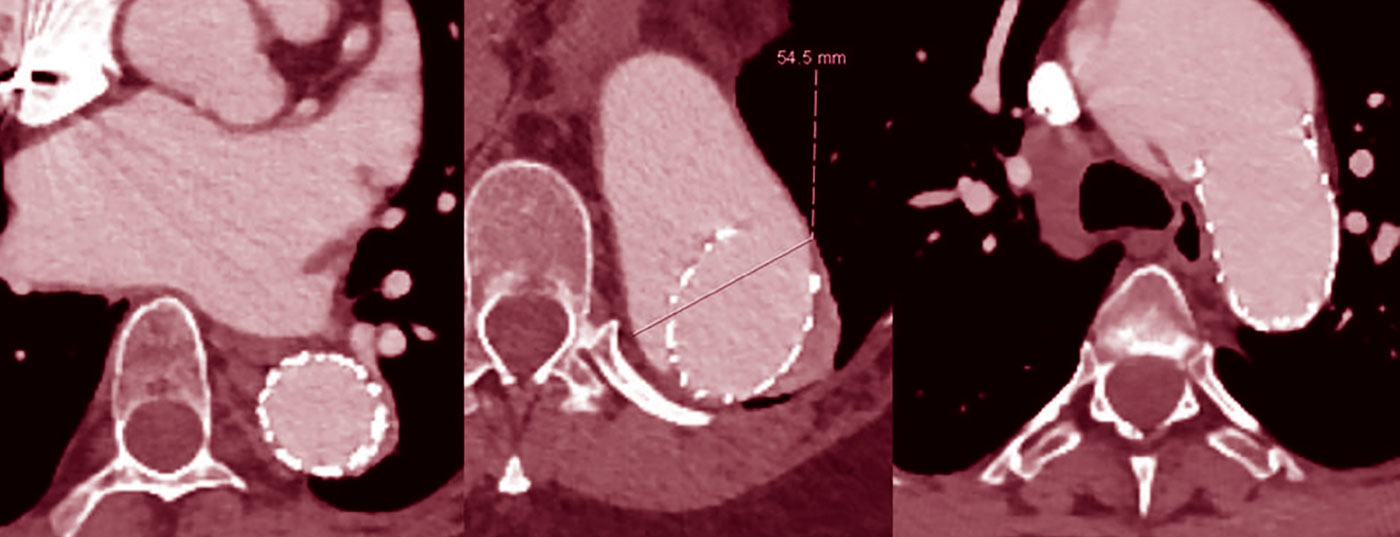

Die chirurgische Behandlung von Patienten mit vererbbaren Bindegewebserkrankungen hat die Vermeidung der Aortendissektion zum Ziel. Denn diese ist für die hohe Mortalitätsrate der Patientenpopulation verantwortlich. Wann ist die Indikation gegeben? Und welche medikamentösen Therapieoptionen gibt es?

• Aneurysma

• Aortendilatation

• Aortendissektion